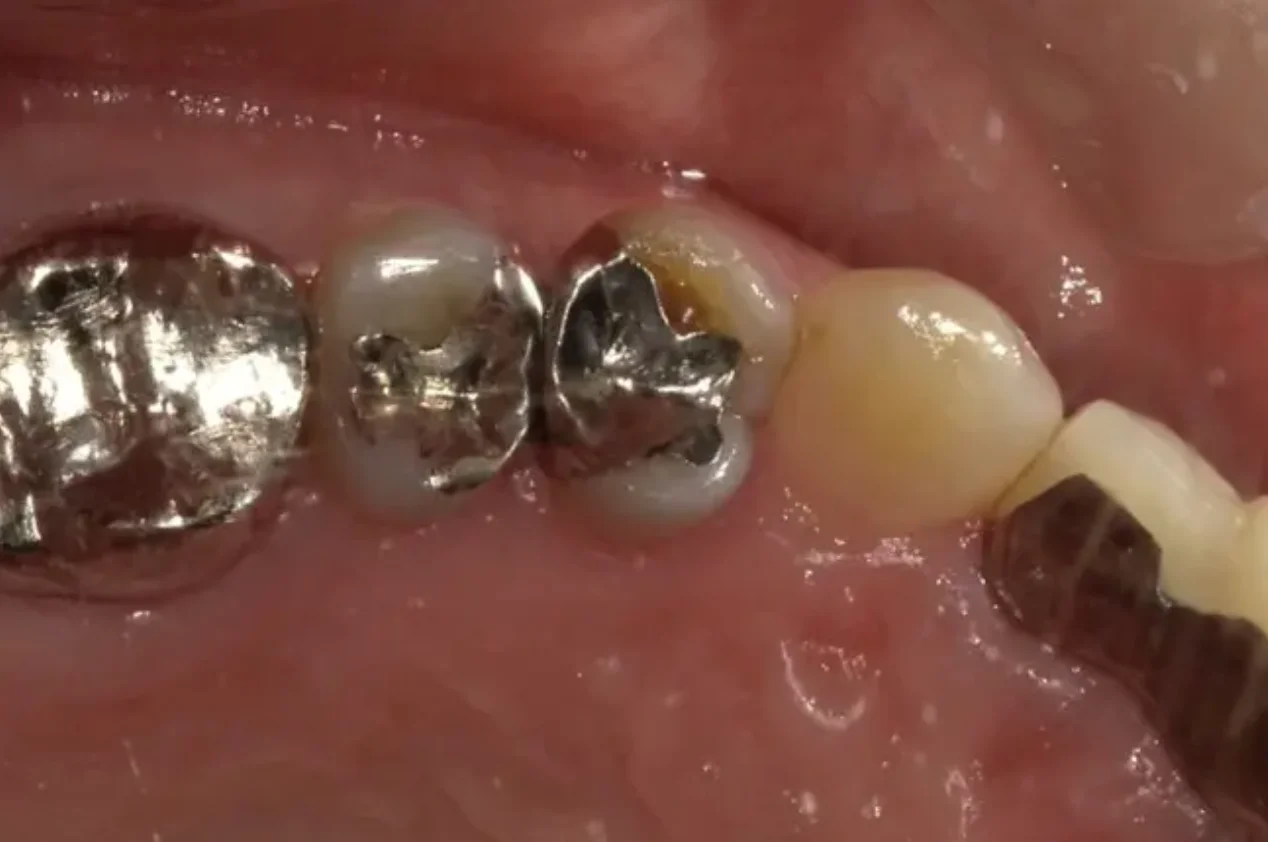

Before

After

銀歯の詰め直し(e-max)(50代女性)

約1ヶ月 3回 / 総額120,000円リスク・副作用:噛み合わせや歯ぎしりが強すぎる場合、セラミックが割れてしまう可能性があります。